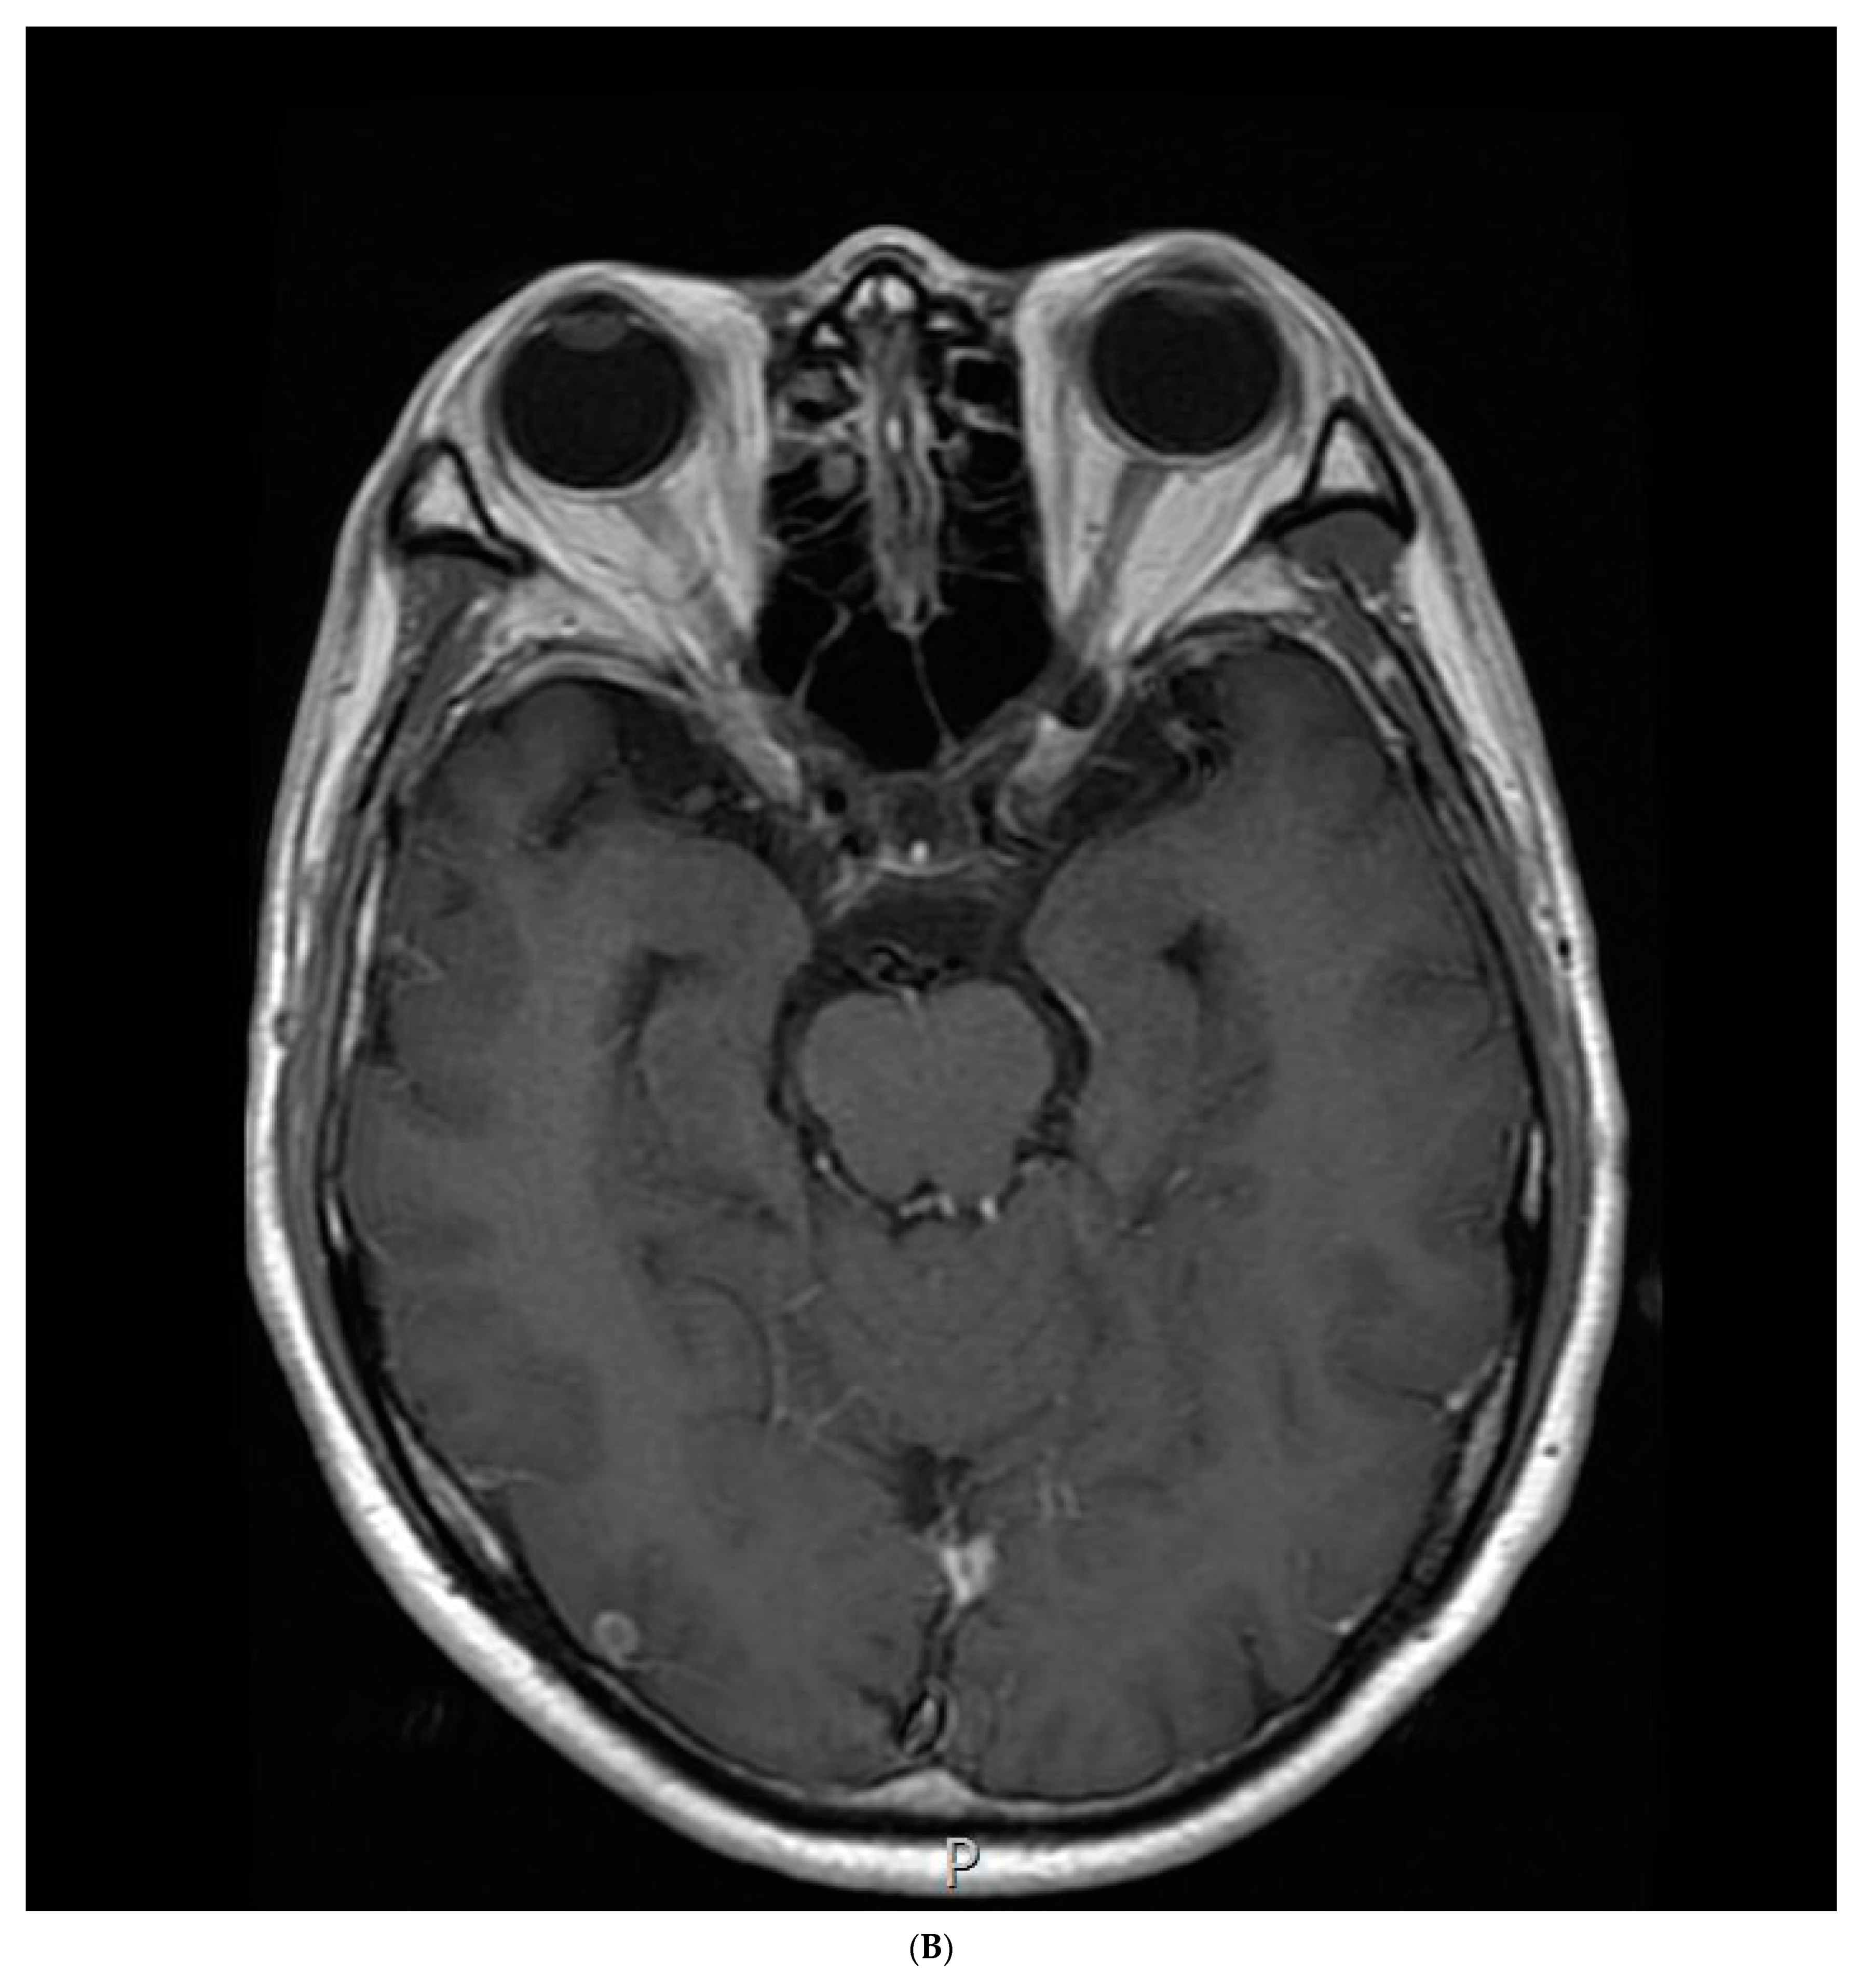

2. Case Report